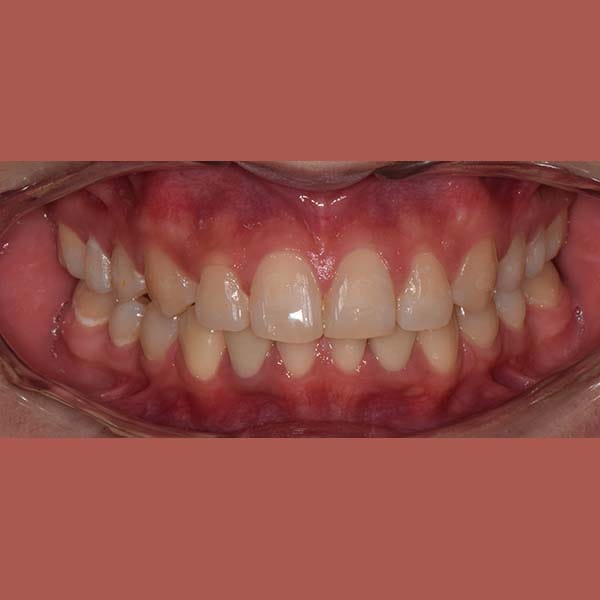

عانت هذه السيدة من وجود عضة عميقة أمامية و غياب خلقي لسنين أماميين سفليين ،بالإضافة لتراكب و عدم ارتصاف الأسنان الأمامية العلوية بشكل جيد – تم فتح مسافة كافية لوضع غرستين سنيتين و تم تصخيح العضة العميقة تقويمياً